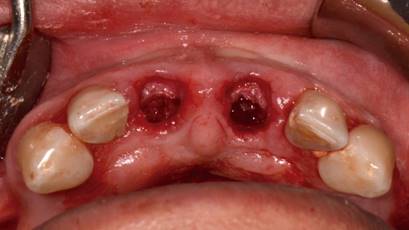

Posteriormente se realizó una impresión de alginato y vaciado en yeso del maxilar, se eliminaron mecánicamente ambos incisivos centrales. Este modelo se digitalizó con un escáner extraoral (3Shape, Trios) y se obtuvo un archivo STL. Luego con esto datos se hizo una coincidencia digital entre el CBCT y el archivo STL, utilizando el software BlueSky plan, (BlueSky bio). Se planificaron dos implantes cónicos de conexión interna de 3.8 x12 mm (Biohorizons), separados de la parte vestibular de las raíces y asegurando su correcto posicionamiento implantario (Img 1). Luego se diseñó una guía quirúrgica en el mismo software, exportada e impresa en ácido poliláctico (PLA) por una impresora de tecnología de deposición de material fundido (FDM) (Duplicator 7, Wanhao, China). Después de la anestesia local, se extrajo la porción coronal de ambos dientes fracturados, luego las partes apicales restantes se dividieron mesio-distalmente con una fresa de diamante de alta velocidad dejando dos porciones. Se retiró la parte palatina y se conservaron 5 mm de la pared vestibular radicular, posteriormente se instaló la guía quirúrgica en posición (Fig 2 y 3).

El protocolo de fresado llegó a los 21 mm de profundidad y a la fresa de 3.2 mm de diámetro. Ambos implantes alcanzaron 40 N de torque, todo bajo un protocolo de cirugía e inserción guiada estricta de implantes (Fig. 4).